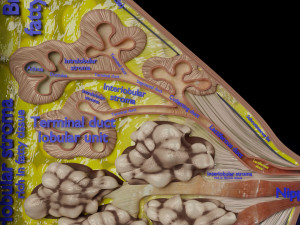

This is a 1:1 scaled model of right breast cut opened in sagittal plane to reveal its internal antomy and histology (schematic). The deeper parts and fascial layers are also depicted to give a very detailed approach to the model. The full layers starting from skin, nipple areola, till intercodtal muscles and ribs are also depicted.

breast mammary gland female chest wall anatomy human medical science reproductive genitalia muscle fascia milk nipple areola subcutaneous fatДо даного товару немає коментарів.